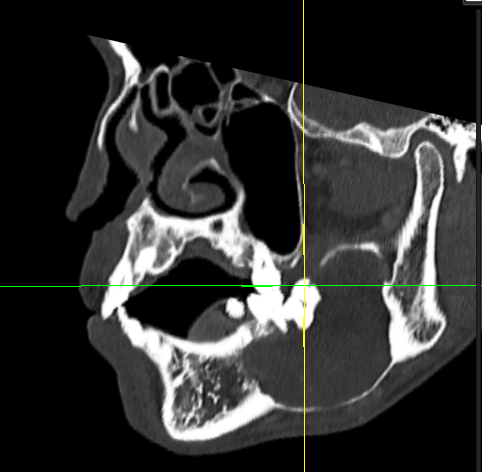

• Association with cysts (fluid-filled sacs) or tumor formation Example: A large cystic lesion (about 60 mm in diameter) associated with an impacted lower third molar (see crosshair photo below).